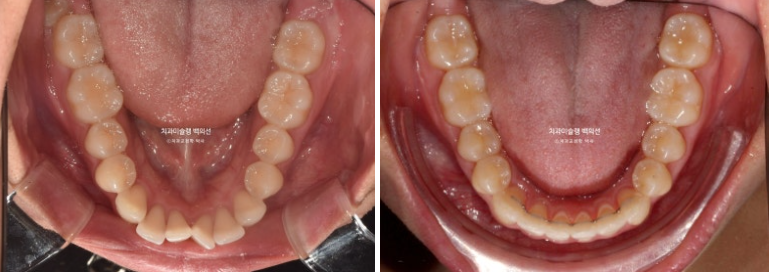

이제 전 후 비교 보겠습니다.

총 치료기간은 2년입니다.

23.09~25.09

큰어금니가 약 2mm 사랑니 공간으로 잘 이동했습니다.